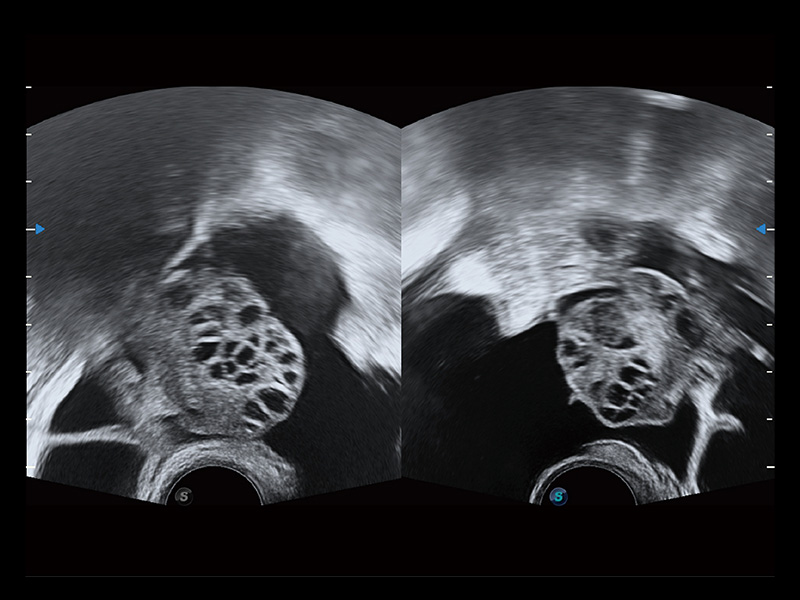

卵巢多囊样改变